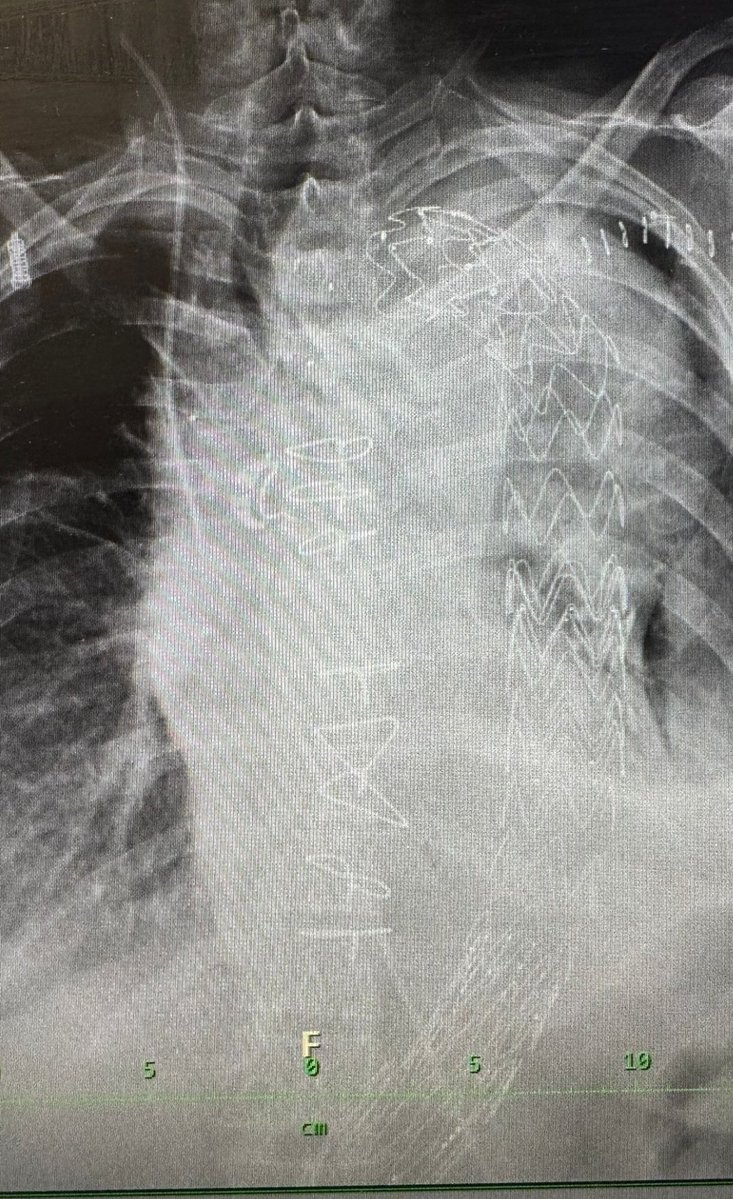

Tohle je prostý rentgen hrudníku, uplne základní diagnostický prvek. Každý jste ho nekdy měli. Tenhle je ale přece speciální, je od pacientky po nasi 8hodinové operaci aorty v před vecer Stedreho dne. Vidíte na nem mimo jine: - vlevo hadicku centrálního zilniho katetru zavedeno z krční žíly do horní dute žíly - kovové klicky (smycky) na hrudni kosti, ktere se nakládají na konec kardiochirurgicke operace, kdy je rozriznuta hrudní kost a je potřeba ji dat dohromady - kozni klipy pod levou klíční kosti, kde byla.rana k tepne a kde jsme měli zavedenou tlustou arterialni linku - v prave části zeshora dolů se táhnoucí trubici, což jsou stentgrafty, kterými jsme nahradili celou vydutemi postiženou aortu od oblouku az po rozdvojeni panevnich tepen. Mladí kolegové se me vzdycky ptají, co tihle lide na letišti, jestli projdou detektory... U téhle pani to vypadá, ze to opravdu bude moci vyzkoušet, a to je ten největší vánoční zázrak. -